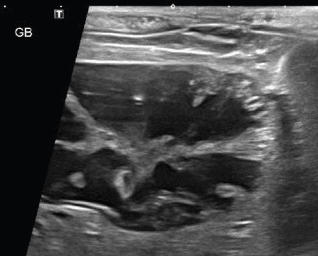

05선명한 초음파 영상 심장/응급초음파 포함, 장기 내부이상에 정확, 빠른 진단이 가능

담낭점액종